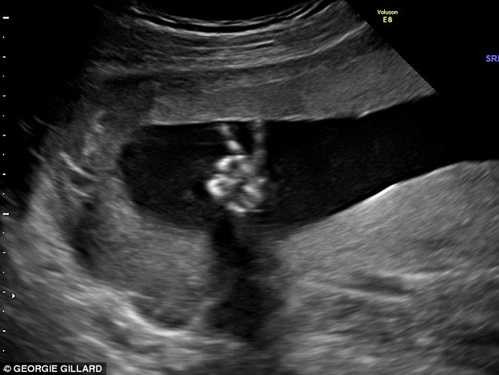

Tuy nhiên, cô đã vô cùng ngạc nhiên khi nhìn trong bức ảnh và thấy hình đứa con trong bụng của mình giơ ngón tay chữ V.

| Thai nhi 20 tuần tuổi tạo dáng chữ V trong bụng mẹ |

Dù rất bất ngờ trước kết quả siêu âm nhưng hình ảnh thai nhi được 20 tuần khỏe mạnh trong bụng mẹ khiến Ed và Dee Parsons, cha mẹ của bé cảm thấy yên tâm, không có gì đáng ngại trong việc chăm sóc bé sau này.